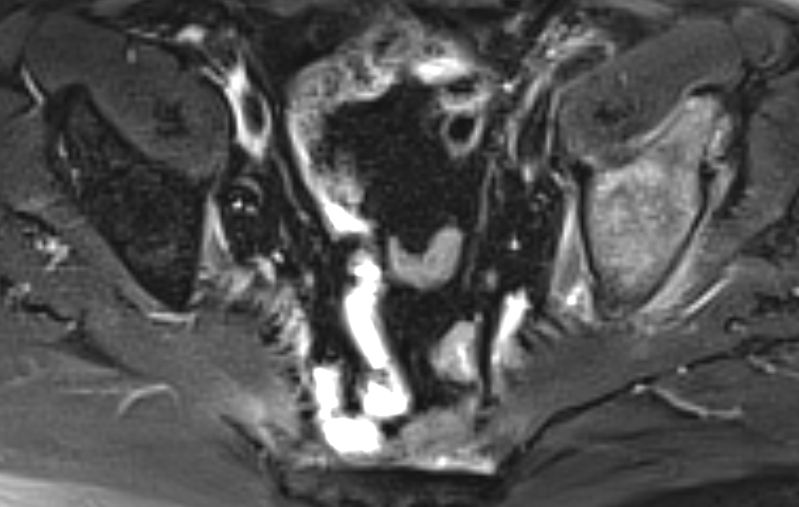

| Knochenmetastasen | 61-jähriger Patient, der vor 2,5 Jahren ein primär hepatisch metastasiertes Rektumkarzinom hatte.

9 Monate FOLFIRI/Erbitux ergaben eine CR der Lebermetastasen.

Mit verschiedenen systemischen und chirurgischen Maßnahmen Tumorkontrolle bis jetzt.

Nun Schmerzen in der linken Leiste besonders beim Treppensteigen.

Das CT zeigt eine Schambeinmetastase mit großem Weichteiltumor.![]() |

Der Weichteiltumor ragt nach caudal in den Adduktorenkanal.![]() |

Cranial ist das symphysennahe Schambein völlig zerstört.![]() |